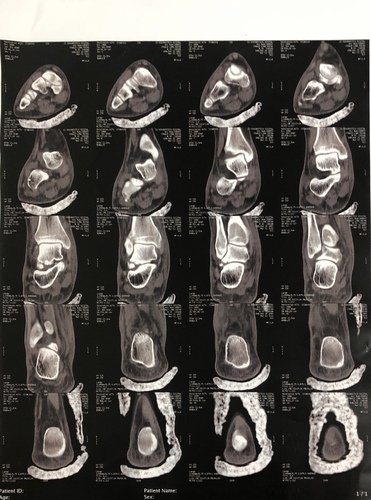

Me chamo Ythalo, tenho 25 anos, há quase um ano no dia 26/02/2022 sofri uma fratura no tornozelo do pé direito, no início pensei que não fosse nada grave, mas ao consultar me informaram que tinha um pequeno derrame articular e houve uma fratura lateral do corpo do tálus. Tive um repouso de 60 dias, e houve um pouco de alívio da dor, voltei as atividades normais, mas ao passar do tempo a dor voltou e foi aumentando cada vez mais. Fiz uma nova consulta e o médico me informou que devo fazer a cirurgia. Hoje me encontro sem trabalhar a 02 meses por não conseguir por causa da dor, e na fila do sus para a cirurgia a 05 meses, mas pelo fato de ainda não terem me chamado para a cirurgia decidi criar a Vakinha para fazer ela o mais rápido no particular, a cirurgia custa 6.000,00 e vou ter que fazer uma nova tomografia e uma nova consulta que vão ficar no valor de 1.000,00. Preciso voltar a trabalhar e voltar as minhas atividades normais, mas isso só será possível após essa cirurgia. Conto com sua ajuda e serei muito grato.